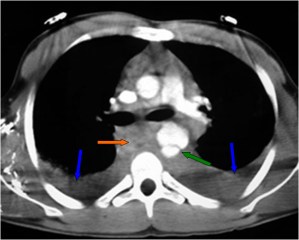

El desplazamiento de la sonda nasogástrica a la derecha (que indica desplazamiento esofágico) en la radiografía de tórax, se ha descrito como el signo más fiable de rotura de la aorta torácica e indica la necesidad de realizar angioTC urgente. La primera imagen muestra el desplazamiento de la sonda (flechas verdes) así como un gran derrame pleural izquierdo (flechas naranjas).

En el corte de TC con contraste vemos la sonda desplazada a la derecha de la línea media (flecha azul), un hematoma mediastínico (flecha verde) provocado por la rotura aórtica (flecha naranja), y un hemotórax izquierdo (flecha amarilla).